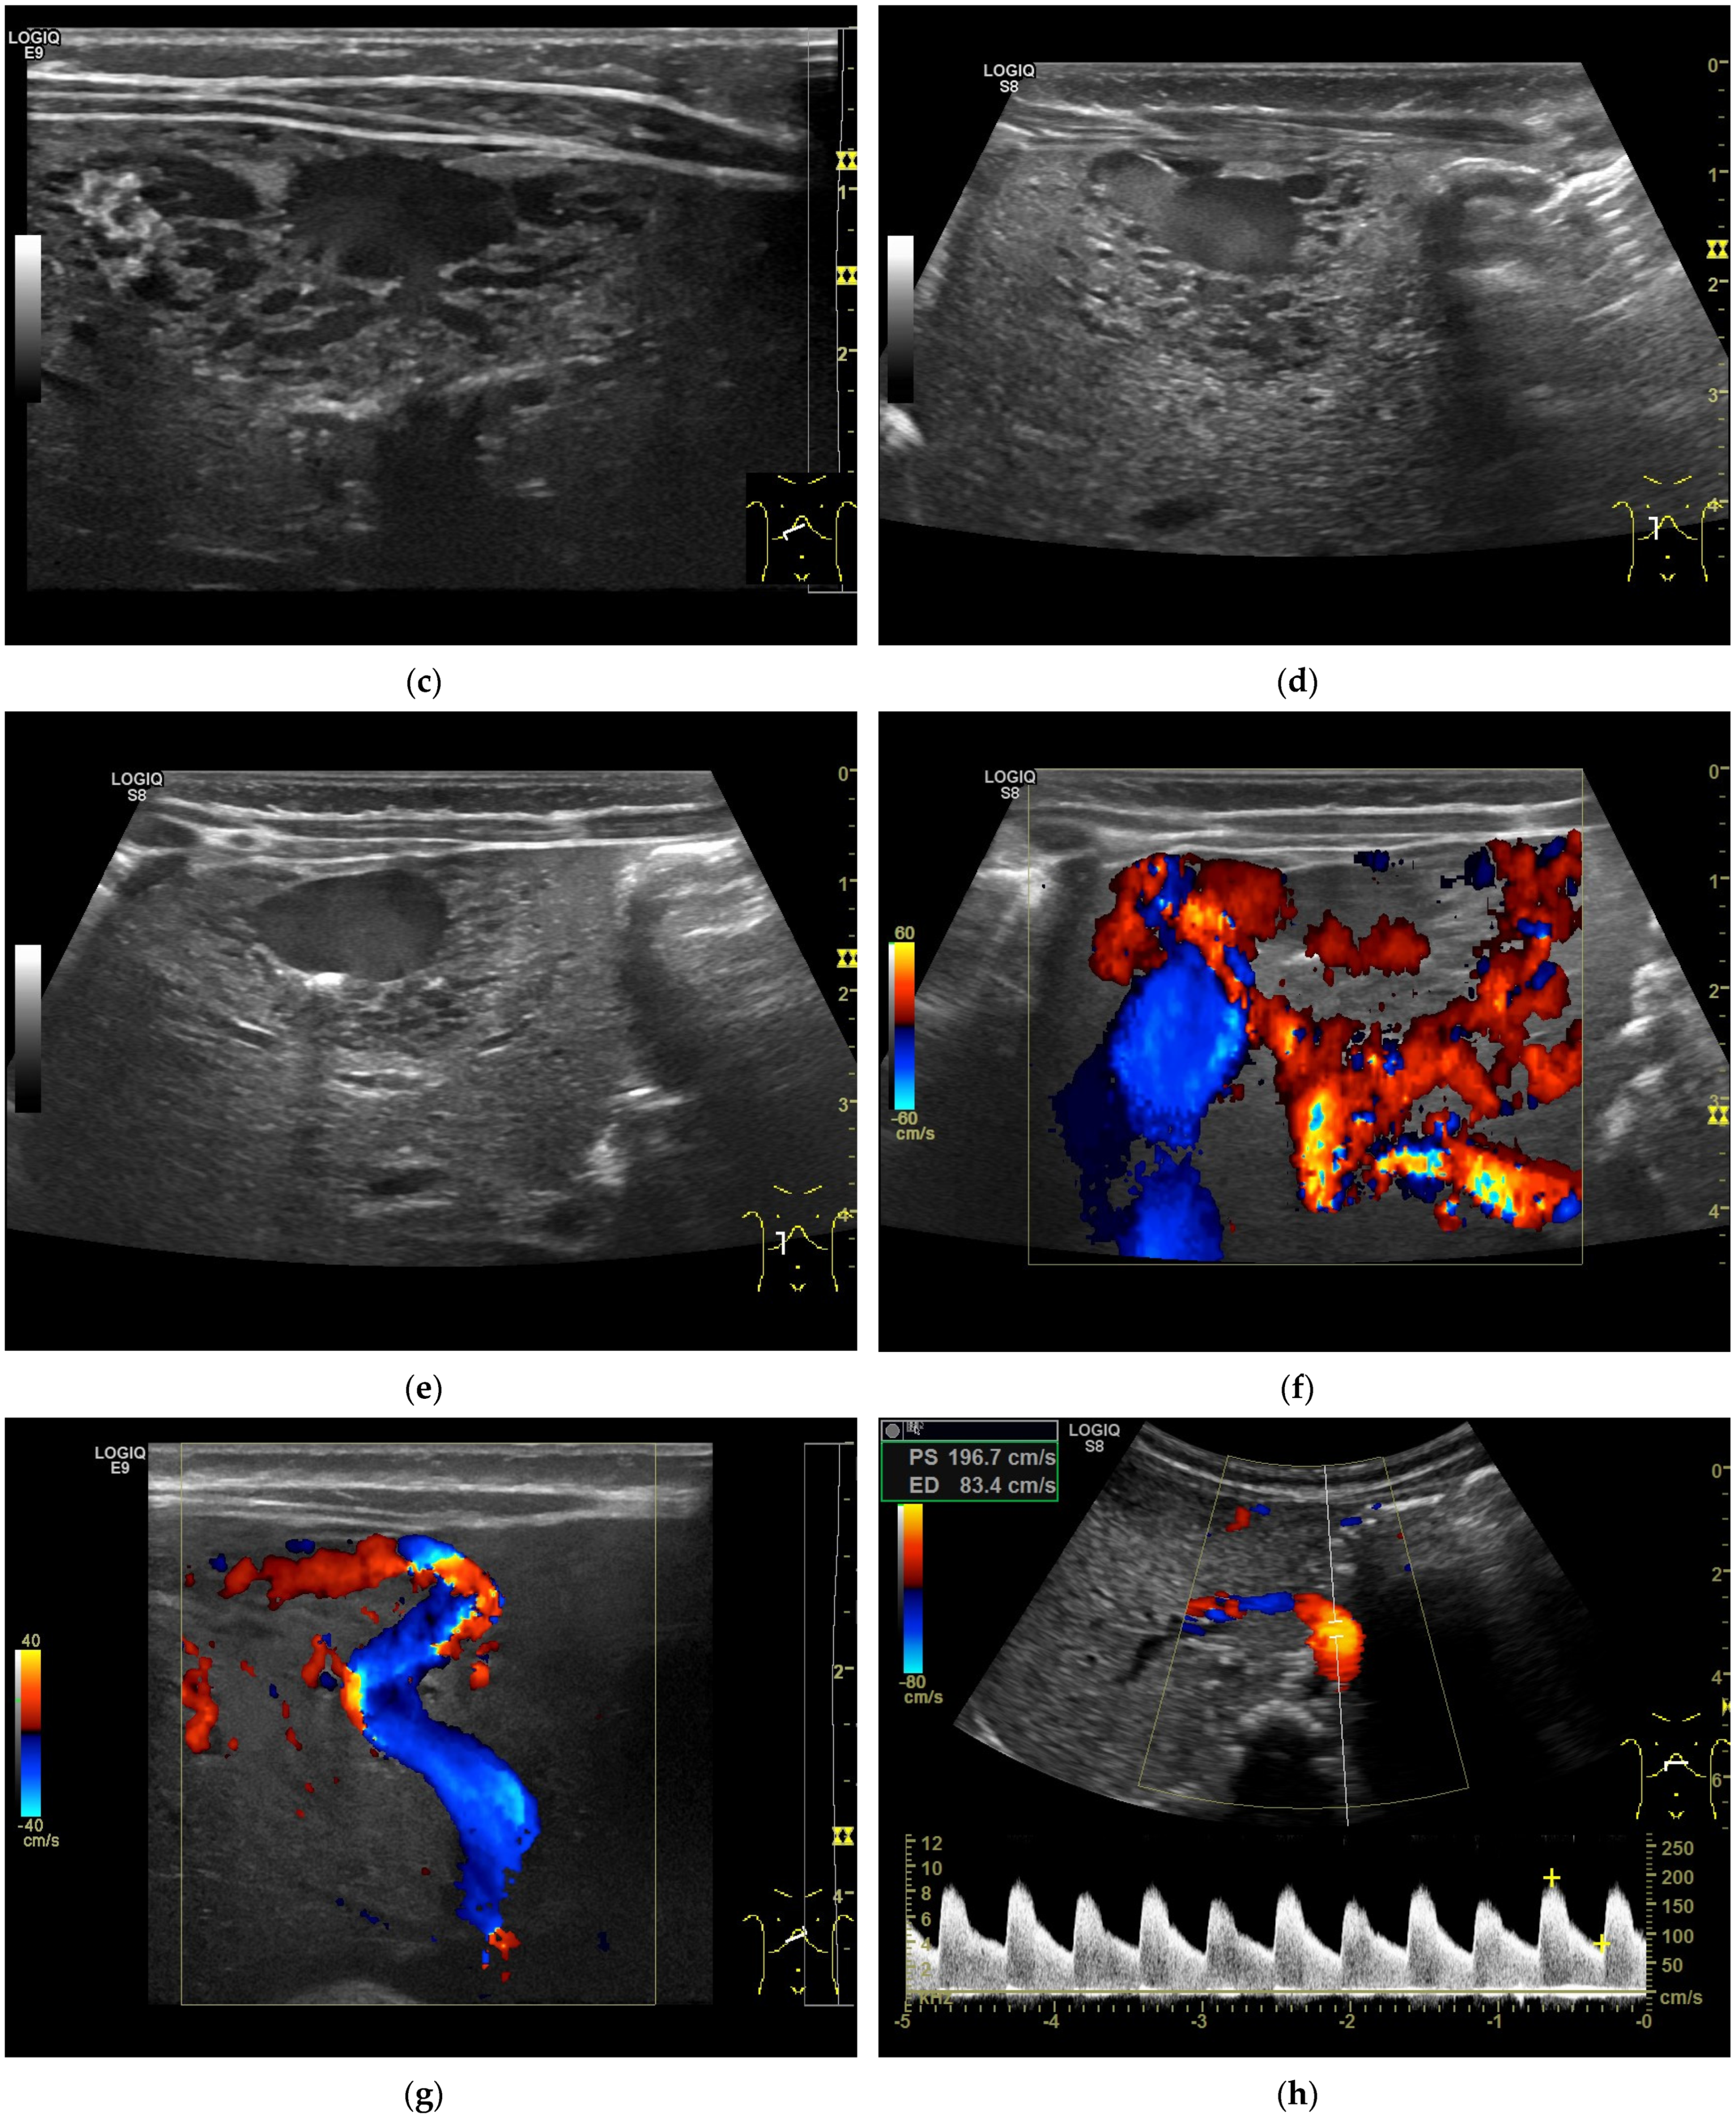

CEUS: CEUS performed on patients with UESL has been rarely reported. UESL might show minimal hypoenhancement due to its complex components, which make it difficult to distinguish from liver abscess. However, biopsy can be conducted under the guidance of CEUS to improve accuracy and ensure the acquisition of positive samples (Figure 2).

Figure 2.

A 5-year-old boy, presenting with a large mass in the left lobe of the liver. B mode shows a heterogenic mass (a). High resolution B mode with a linear probe clearly reveals multiple cavities representing hemorrhage and necrosis within the mass (b). CEUS in the arterial and early portal venous phases revealed rapid peripheral enhancement with prominent centripetal fill-in and non-enhancing areas (c–e). Late washout after two minutes could be documented (f). Needle biopsy and histological evaluation revealed a highly malignant (G3) liver embryosarcoma.